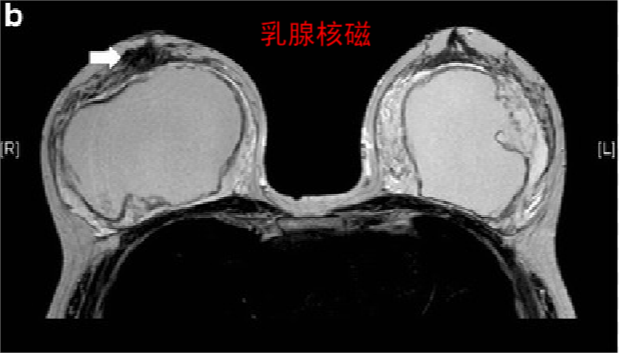

7植入物患者的乳房 MRI

乳腺MRI 是检测乳房植入物破裂的最敏感技术,植入物的存在不会影响 MRI 对乳腺癌检测的敏感性 。

注意:在没有症状的情况下,不需要通过乳房 MRI 筛查乳房植入物的完整性。